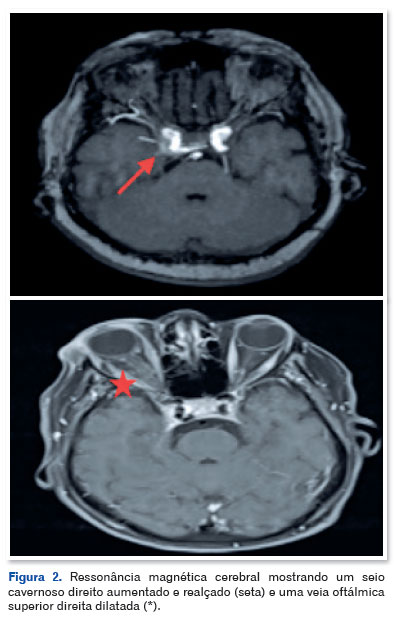

A ressonância magnética craniana (Figura 2) e a angiografia por ressonância magnética (Figura 3) revelaram estruturas vasculares tortuosas e ectásicas adjacentes à parede posteromedial do segmento intracavernoso da artéria carótida interna direita, bem como dilatação assimétrica da veia oftálmica superior no mesmo lado e proptose direita grau II. Esses achados foram consistentes com o diagnóstico de FCC.